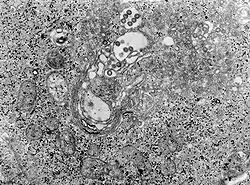

![]() Зображення тканини, що була заражена вірусом гарячки Рифт Валлі (трансмісійна електронна мікрофотографія) Зображення тканини, що була заражена вірусом гарячки Рифт Валлі (трансмісійна електронна мікрофотографія) | |